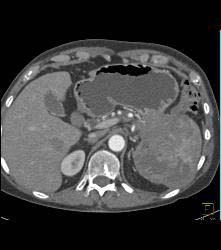

Pancreatic Cancer Invades the Spleen